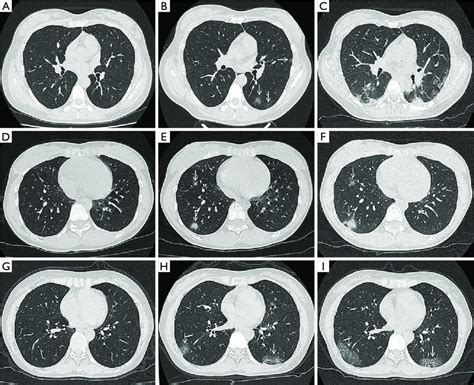

CT Scans: A Closer View

Computed Tomography (CT) scans are incredibly important for evaluating Mesothelioma On Imaging. They provide detailed cross-sectional images of your chest or abdomen, revealing abnormalities much more clearly than X-rays. With a CT scan, doctors can observe:

- Pleural thickening and nodularity, especially if it's circumferential.

- Pleural effusions, assessing their size and extent.

- Invasion of nearby structures like the chest wall, diaphragm, or mediastinum.

- Enlarged lymph nodes, which could indicate spread.

These details are crucial for staging the disease and planning treatment.